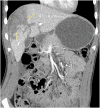

Blunt abdominal trauma is a common cause of solid organ injury in children. Nonoperative management has been established as the standard of care for suspected liver and spleen injuries without peritonitis. Major ductal injury with resultant biloma is a rare complication of nonoperative management of blunt liver injury. Endoscopic retrograde cholangiopancreatography (ERCP) and/or percutaneous drain placement are considered to be safe adjuncts in the management of these bile leaks. However, in the rare cases of persistent bile leak, further nonoperative alternatives have not been reported. In this case report we present a novel multidisciplinary approach to managing persistent bile leaks in blunt liver injury.